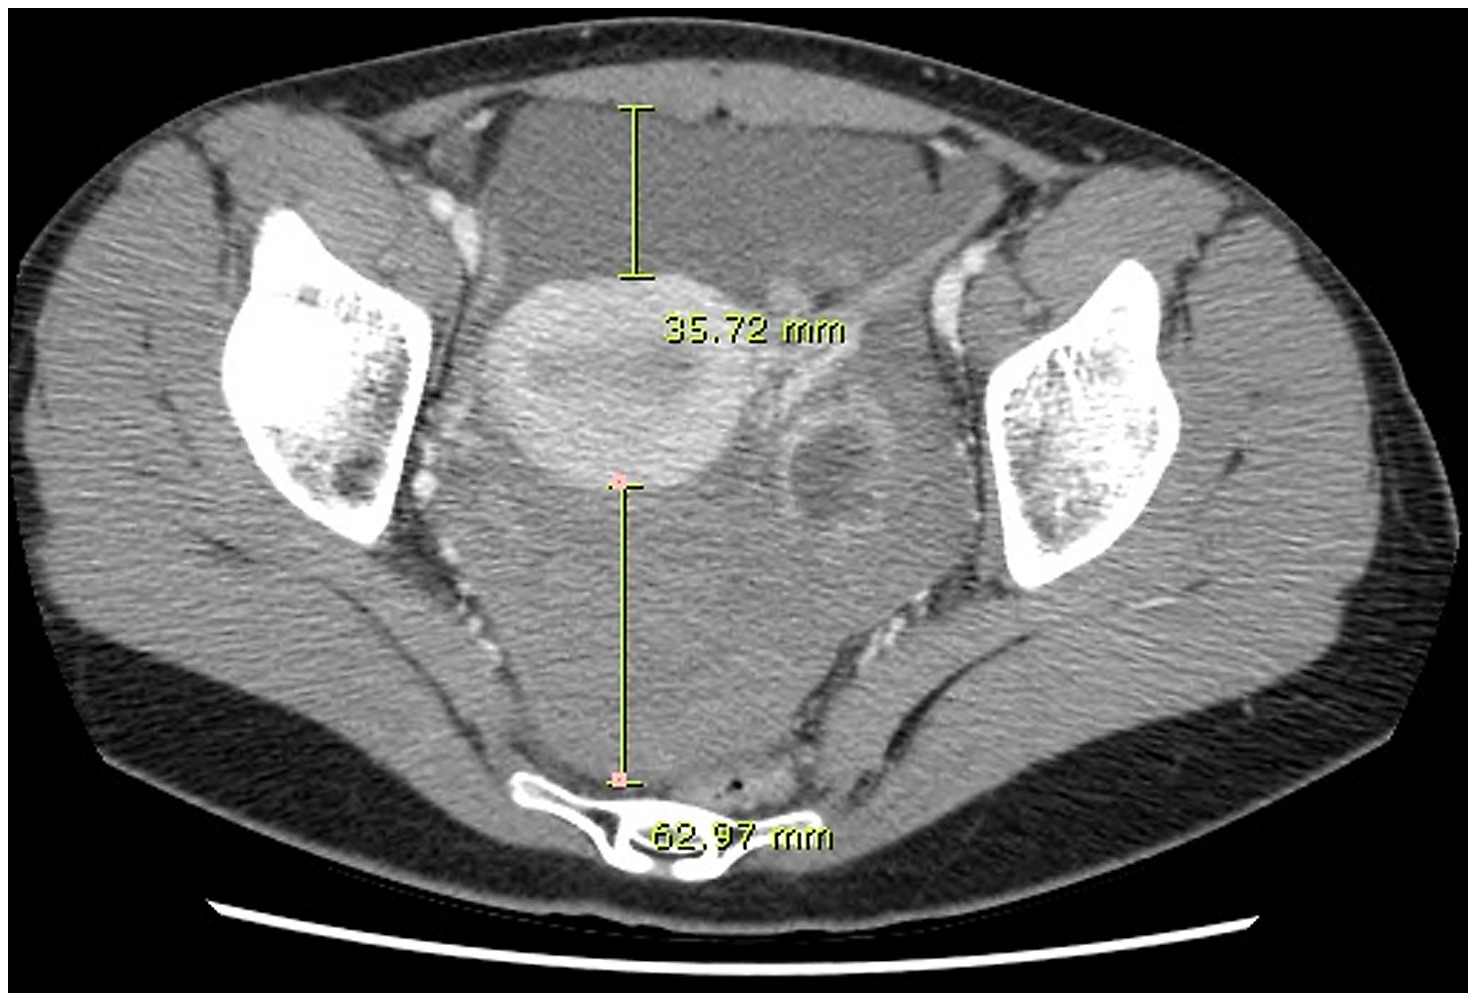

Ct Quantification Of Hemoperitoneum